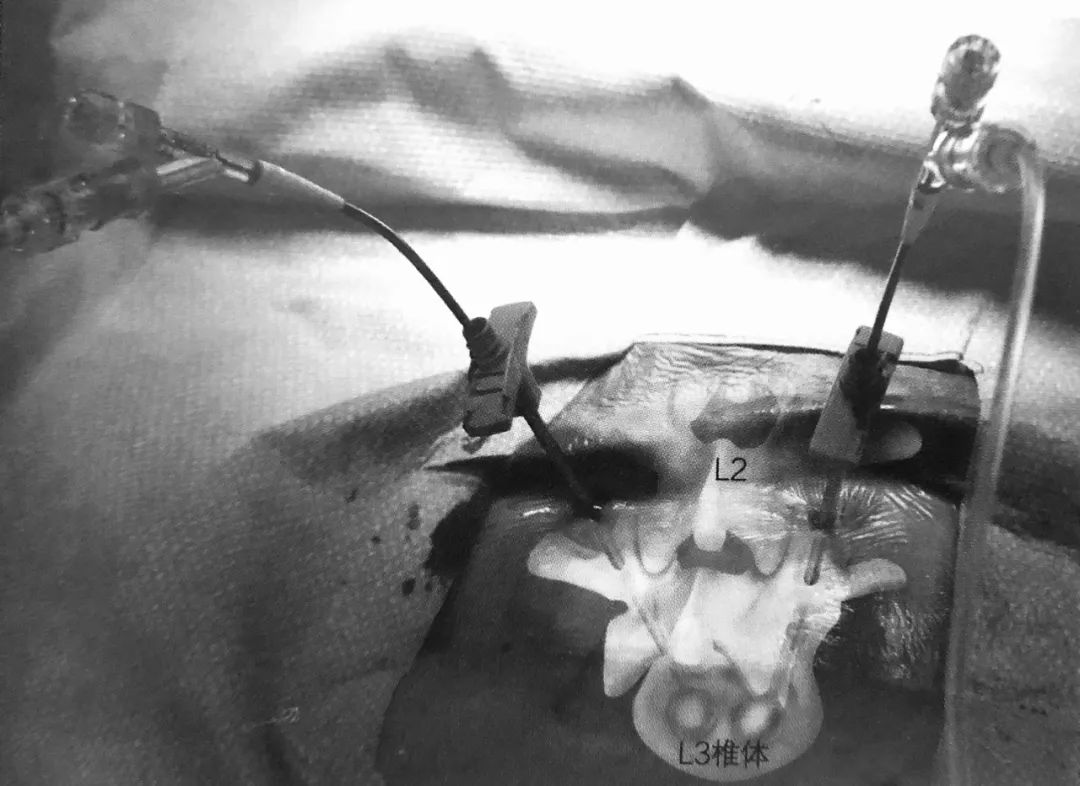

3. 球囊套管的开口点应位于椎弓根的 10 点或 2 点位置即上外侧角,取决于左右。将置入通道设计于该处可保证其离神经根最远。如前后位片所示插入通道,侧位片上套管通过椎体后缘线之前不能越过椎弓根内壁。

4. 通道开口点位于关节突关节外侧,这样可以避免损伤关节囊。